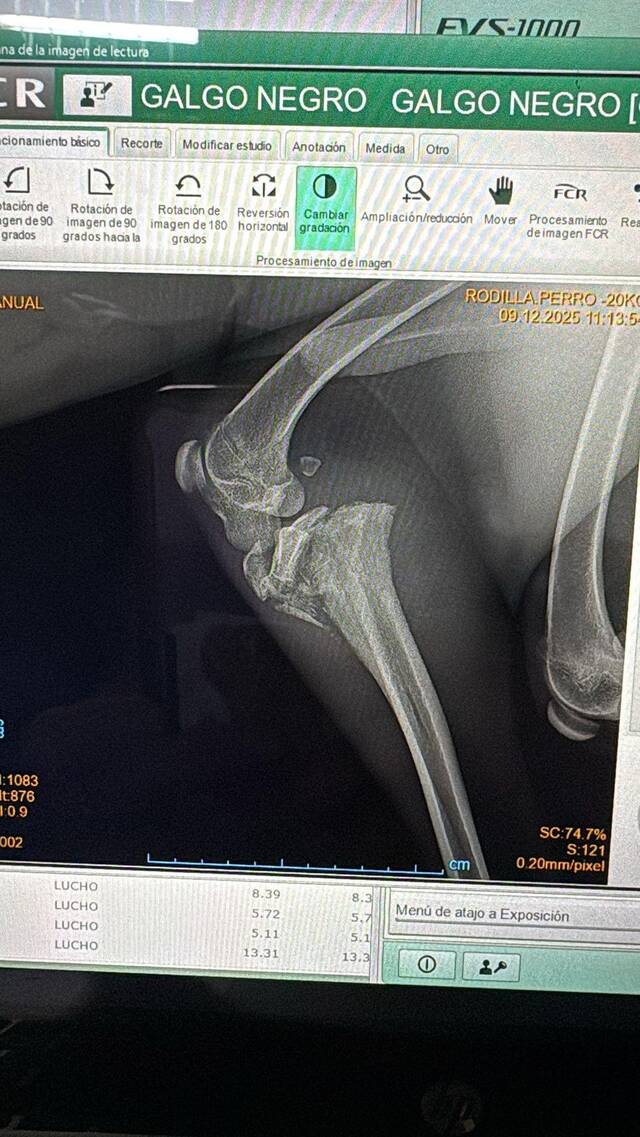

Ethan wurde an einer Autobahn entdeckt, mit gebrochenem Bein, angebunden und völlig hilflos. Niemand weiß, wie lange er dort ausharren musste. In der Tierklinik dann der nächste Schock: Ethans Bein ist mehrfach und so kompliziert gebrochen, dass es auch durch eine Operation nicht gerettet werden könnte.